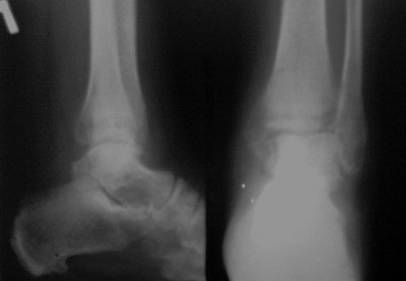

перелом лодыжек трёхмесячной давности

Здравствуйте, коллеги! Ко мне на консультацию обратилась больная 54 года, 110 кг весом.

Травма 3 мес. назад, лечилась амбулаторно в гипсовой лонгете. Как поступить далее? Я планирую ORIF, внутреннюю лодыжку - спицами и проволокой, наружную - пластиной 1\3 трубки. Позиционный винт для фиксации синдесмоза. Как Вы считаете, это верная тактика? какой вероятен исход? Какие имеются нюансы в этом сроке, особенности техники? Может стоит вначале разработать движения в голеностопе? Нужен ли гипс после операции ?С уважением Д.Б.

Правый снимок или размыт, или, что вероятнее - все срослось. Лечите деф. артроз, коллега. А металл, металл в металлолом. Или снимки более четкие. С уважением.

Снимки конечно нечитаемые. Оставлять так конечно нельзя, не устранен подвывих. Но нужно внимательно оченить зоны перелома, т.к. срок достаточно большой. Может так получиться, что вы пойдете на МОС, а найти зоны переломов будет очень сложно, придется отломки разъединять. Хотя в личной практике часто встречаю подобные переломы 2,3,4 мес давности, и когда открываешь - ВООБЩЕ нет признаков сращения, что мне пока непонятно. Если все таки нет сращения рекомендовал бы наружную пластиной с позиционным с концевой резьбой (или рассверлить fibula до ширины резьбы, обязательно зацепившись за внутренний кортикальный слой tibia), а внутреннюю конечно винтом, отломок позволяет. Но есть еще один момент, даже если нет сращения, то зона синдесмоза наверняка уже заполнена рубцовой тканью, поэтому просто затянуть его не получится, нужно или делать ревизию или вообще идти на ВКДО.